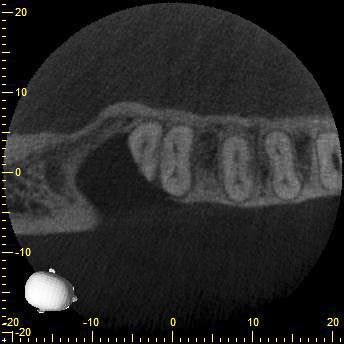

KD47-4

Und das hier war einfach nur Pech…